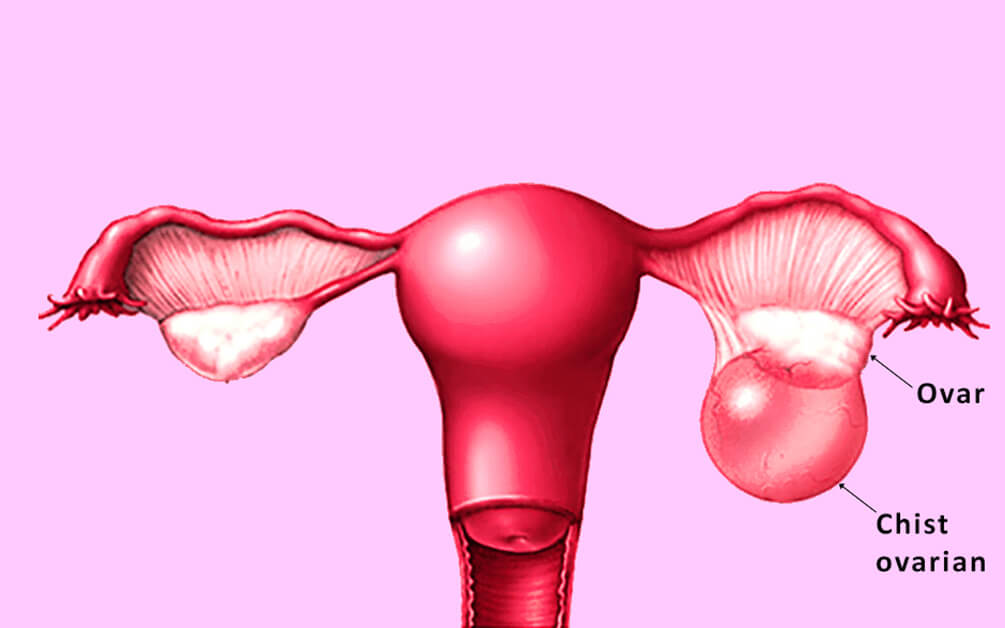

Chisturile ovariene

Definiție

Chistul ovarian este o formațiune dezvoltată din ovar care are perete propriu și conține, cel mai frecvent un lichid, dar poate conține și elemente solide - țesut sau o combinație. Chisturile ovariene apar foarte frecvent, dar de cele mai multe ori nu cauzează simptome și dispar în câteva luni fără a necesita tratament.

Tipuri și cauze

Chisturile ovariene pot fi clasificate în funcție de anumite criterii: